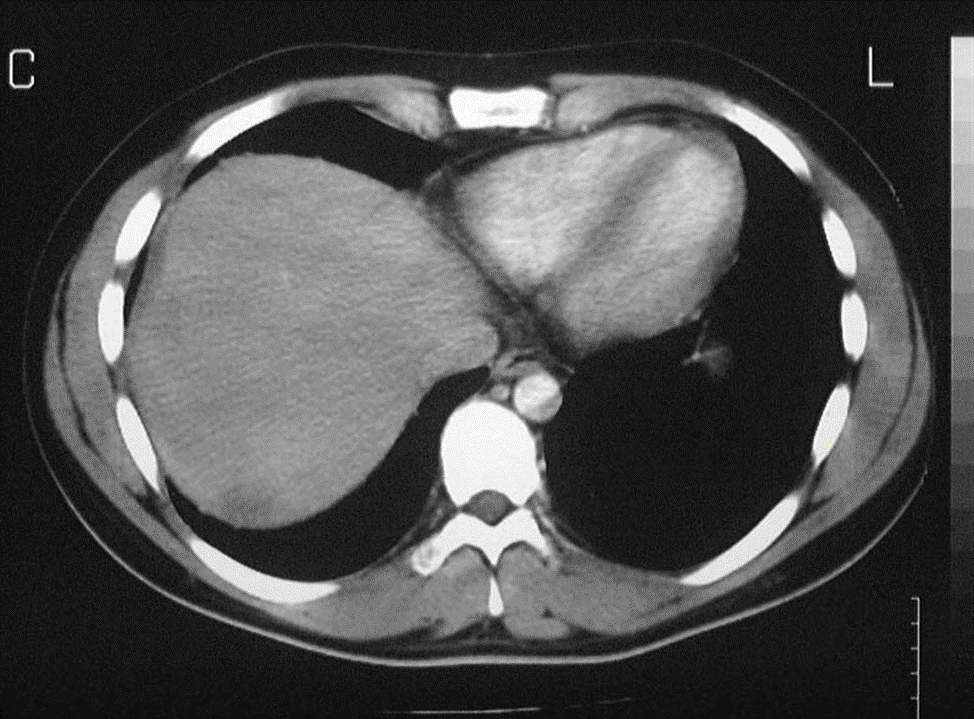

Ảnh minh họa chỉ định chụp CT Scan

Ảnh chụp CT Scan rõ nét